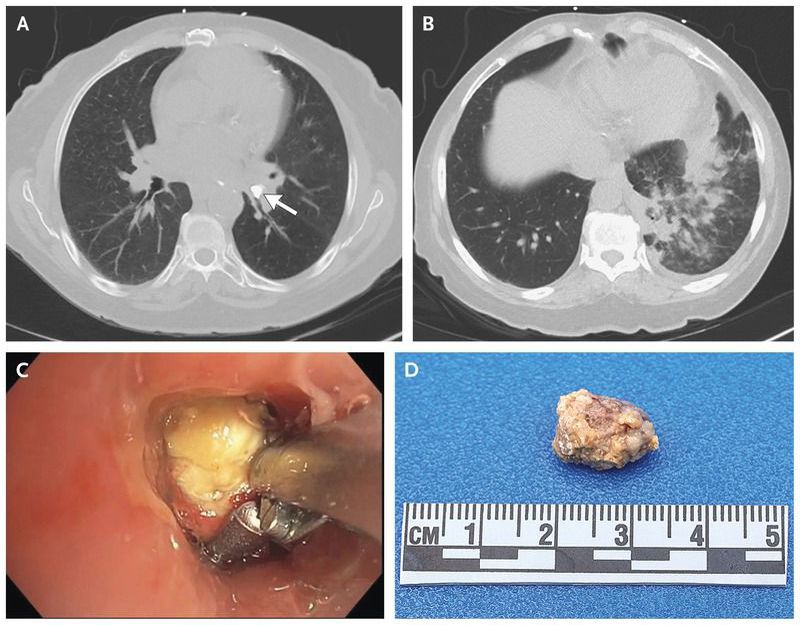

A 68-year-old woman presented to the emergency department with a 3-day history of worsening shortness of breath, wheezing, dry cough, fevers, and chills. Her oxygen saturation was 96% while she was breathing ambient air. Pulmonary examination revealed crackles in the left lower lobe. Computed tomography of the chest showed an obstructing broncholith in the bronchus of the left lower lobe (arrow in Panel A, bone-window setting) with peribronchial ground-glass and patchy consolidation (Panel B, lung-window setting). Flexible bronchoscopy revealed a loose broncholith that was obstructing the proximal bronchus of the left lower lobe (Panel C). The broncholith, which measured 1.00 by 1.45 cm (Panel D), was grasped and gently retracted. Broncholiths are most commonly formed by peribronchial lymph nodes that calcify and migrate into the lumen of the bronchus. Lymphatic calcification can develop after chronic granulomatous infection, such as histoplasmosis or tuberculosis. Cultures of bronchoalveolar-lavage fluid were negative for mycobacterial, bacterial, and fungal organisms. An interferon-gamma release assay to test for evidence of previous tuberculosis exposure was negative, and serologic testing for histoplasmosis was negative. The patient was treated with antibiotics for postobstructive pneumonia, and her symptoms resolved.